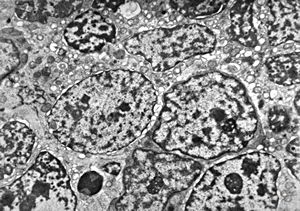

M,50y. | Pneumocystis carinii - lung